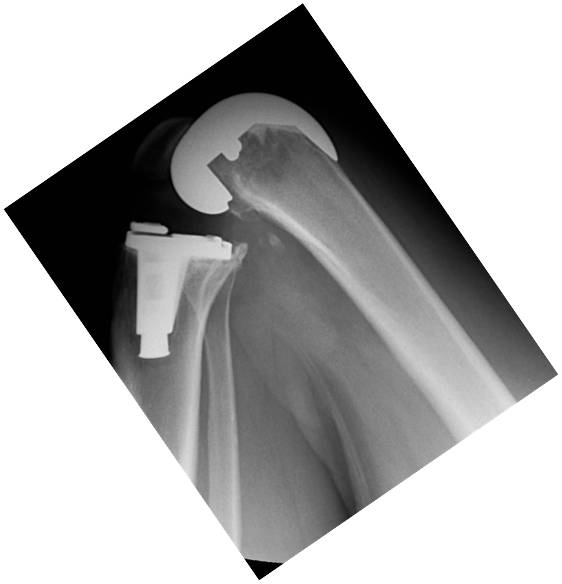

Introducción: El objetivo de este trabajo fue analizar los resultados funcionales y el rango de movimiento entre tres grupos de pacientes con artroplastia total de rodilla: dos utilizando prótesis de alta flexión y el otro con un diseño convencional. Materiales y Métodos: 64 pacientes fueron operados con prótesis total de rodilla Zimmer NexGen®, y 34 pacientes operados con Optetrack ® de alta flexión. Luego de la exclusión de pacientes; 22 pacientes (grupo A) fueron tratados con diseño de alta flexión de Zimmer, 21 pacientes (grupo B) tratados con prótesis Zimmer convencional, y 25 pacientes (Grupo C) con artroplastia Optetrack® PS. La evaluación funcional se realizó con el Knee Society Score, el Western Ontario and McMaster Universities osteoathritis index y la escala analógica visual. Resultados: En el posoperatorio, el promedio de flexión máxima del grupo A subió de 99° a 113º, con un aumento promedio de 14º, en el grupo B de 106° a 118º con una ganancia promedio de 12º y en el grupo C de 110° a 111° siendo la ganancia de 1°. Los resultados funcionales evaluados con KSS y el WOMAC presentaron mejorías en los tres grupos. Conclusión: Las evaluaciones clínicas funcionales son favorables en los tres diseños evaluados. Este estudio muestra que no hay diferencias significativas en la flexión final lograda, y resultados funcionales entre los dos primeros diseños entre sí, si siendo estos significativamente superiores al diseño del tercer grupo luego de un año de seguimiento. Palabras Claves: Prótesis total de rodilla, prótesis de alta flexión, prótesis convencionales, rango de movilidadDescargas